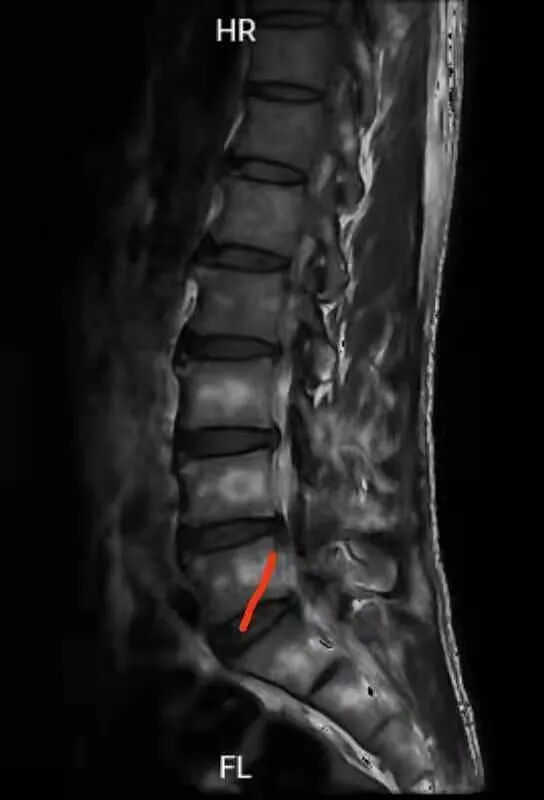

术后MRI影像图片

术后病人轻松下地自行走回病房